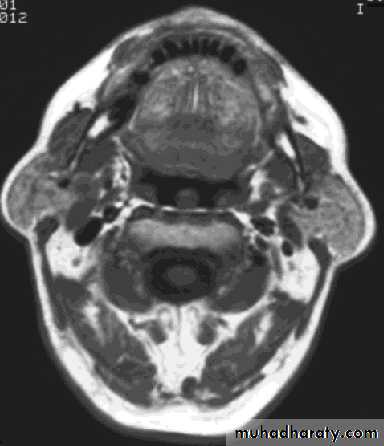

ComparisonsMRI image

CAT image

head

Compare bone and soft tissue density